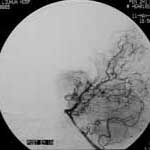

二、脑动静脉畸形(AVM)

---- Spetzler对AVM的分级方法已越来越多地被人们接纳和采用。脑AVM最危险的症状之一是出血。AVM每年的出血率为3%~4%,第一年内再出血约6%。每次出血的致残率为30%,病死率为12.5%,而积极治疗的总残废率加病死率在10%以下。

血管内栓塞对于单支或少数供血动脉的AVM,特别是新近出血的病例,可以达到微侵袭、痛苦小、疗效迅速的目的。

近来改变栓塞方式,将导管直接放置 畸形血管团内,注射NBCA胶,可使畸形团的解剖 治愈率提高至27%。再加上更细、超滑的微导管问世,栓塞的并发症更为降低。针对大型、功能区 的AVM栓 塞可缩小其体积,改善血液动力学分布,以利于显微外科技术切除或放射外科治疗,是后二者的重要辅助手段。